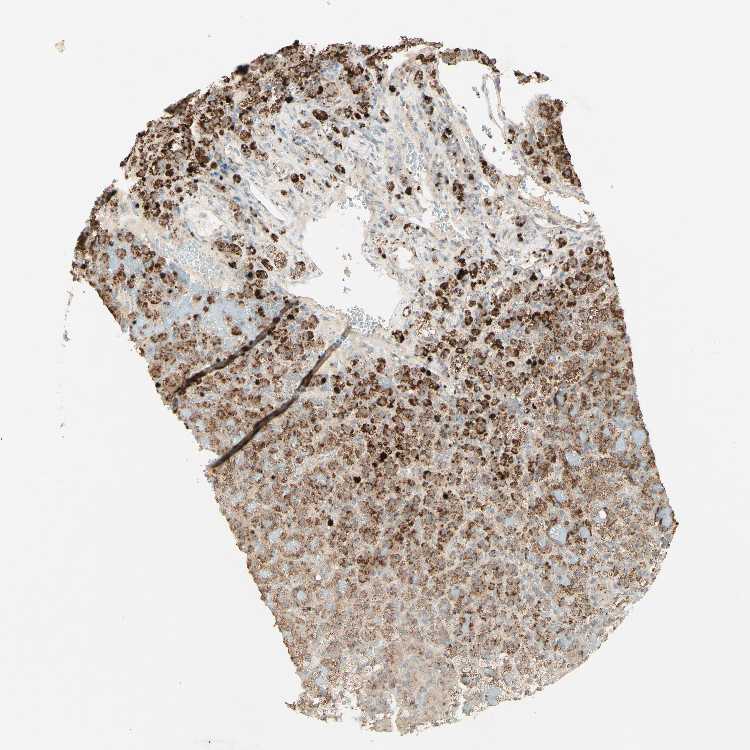

ADRENAL GLAND - Antibody stainingi

Antibody staining in the annotated cell types in the current human tissue is reported as not detected, low, medium, or high, based on conventional immunohistochemistry profiling in selected tissues. This score is based on the combination of the staining intensity and fraction of stained cells.

Each image is clickable and will lead to virtual microscopy that enables deeper exploration of all samples and also displays staining intensity scores, fraction scores and subcellular localization as well as patient and tissue information for each sample.

Antibody HPA010008Antibody HPA010665

Glandular cells MediumHigh